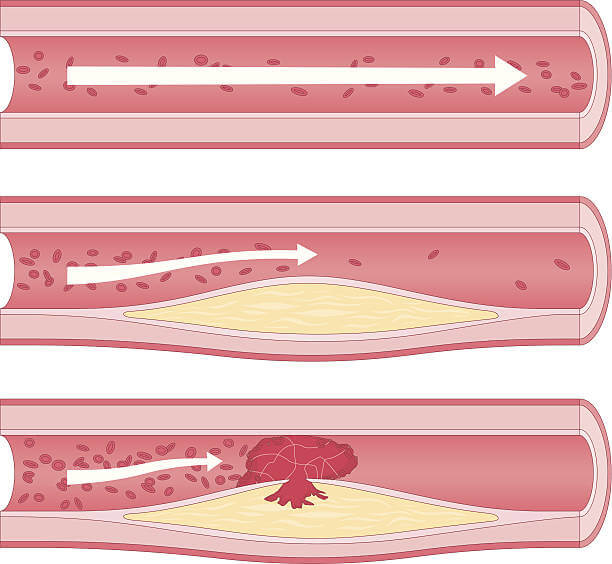

콜레스테롤이 혈관 벽에 쌓이면 "플라크" 라고 불리는 지방 침착물이 형성됩니다. 이 플라크는 동맥 벽 내부를 좁게 만들어 혈액 흐름을 제한합니다. 협심증은 주로 심장에 산소와 영양분을 공급하는 관상동맥에서 발생하므로, 관상동맥에 플라크가 형성되면 심장에 충분한 혈류가 공급되지 못해 협심증 증상이 발생할 수 있습니다.

플라크 형성

플라크가 점차 성장하면서 혈관 내부를 좁혀나갑니다. 이로 인해 혈액 흐름이 제한되고 심장에 산소와 영양분을 공급하는 관상동맥의 혈류가 감소합니다.

혈전 형성

플라크의 표면이 파열되면 혈소판이 그 곳에 집착하여 혈전(응고체)이 형성될 수 있습니다. 혈전은 동맥을 완전히 막을 수 있어 심장에 심각한 손상을 초래할 수 있습니다. 이렇게 동맥 경화증이 진행되면 관상동맥의 혈류가 감소하고, 심장 근육에 충분한 혈류가 공급되지 못하면서 협심증이 발생합니다.